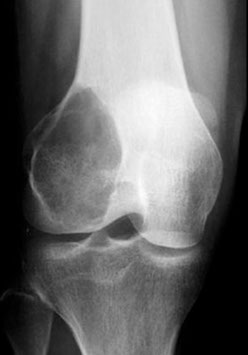

Rare (1 in 1 million); MC in epiphyseal end of long bones (just like chondroblastoma, and the rare clear cell chondrosarcoma), esp around the knee of 20-40 yo

- is a fairly common lesion

- can only be seen in pts c skeletal maturity (***Gotta grow up to be a Giant***)

Although benign, is locally aggressive (10% have malignant transformation) and can met (even if it looks b9!)

Imaging: "Double bubble" or "soap bubble", usually on both epiphysis and proximal metaphysis

- can look malignant on radiology (in 1/4, cortex destroyed and extends into ST), though generally has no tumor matrix production or periosteal production

Micro: Spindle-shaped cells c MNGCs with uniform scattering

- mononuclear cells and GC's have similar nuclei and uniformity of cytologic features, can have 50-100 nuclei per cell,  lacking atypia